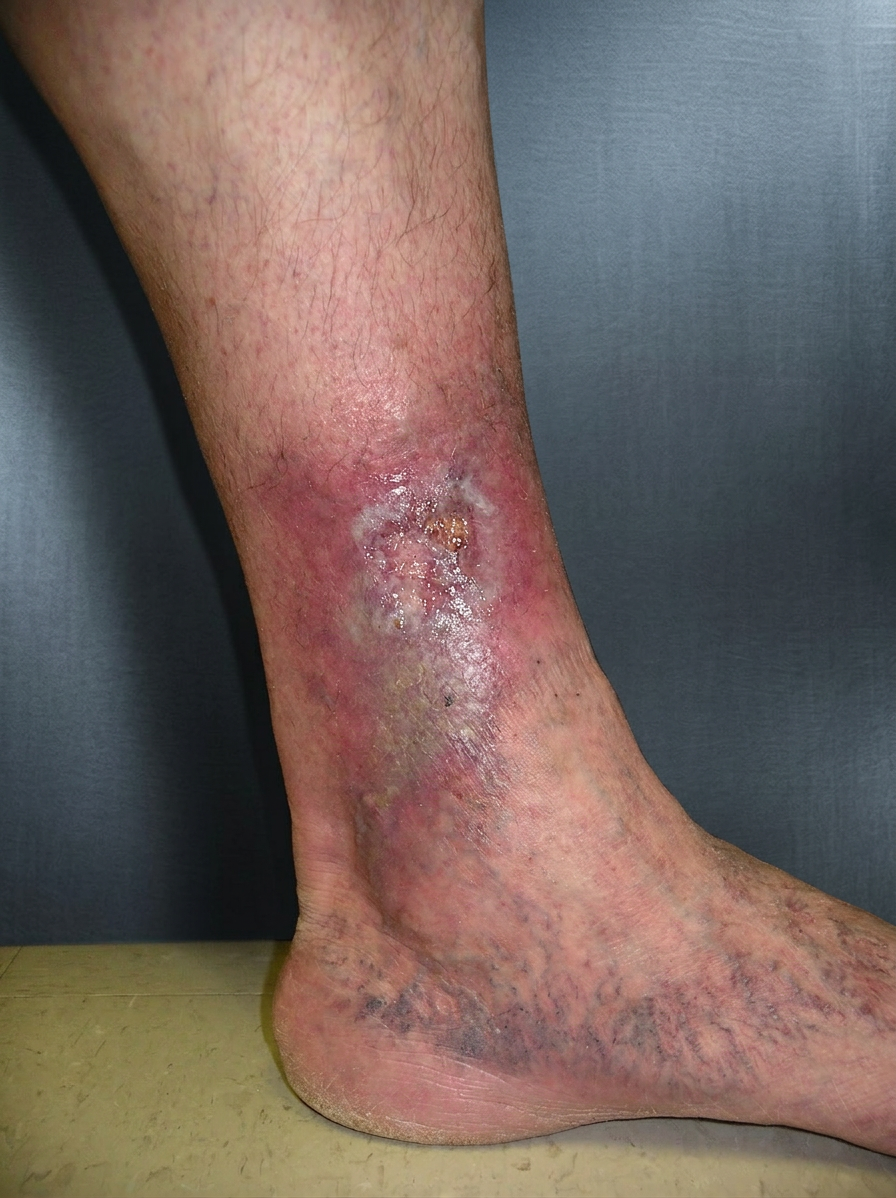

Varicose Leg Ulcers

What is a Varicose Ulcer?

A varicose ulcer (venous ulcer) is a form of venous ulcer caused by long-standing varicose veins and chronic venous disease. Enlarged and twisted veins allow blood to flow backward and pool in the lower leg, increasing pressure and damaging the skin over time.

These ulcers usually appear around the inside of the ankle and are often associated with visible bulging veins, leg heaviness, aching, swelling, and skin changes such as redness, dryness, or dark staining before the ulcer forms.